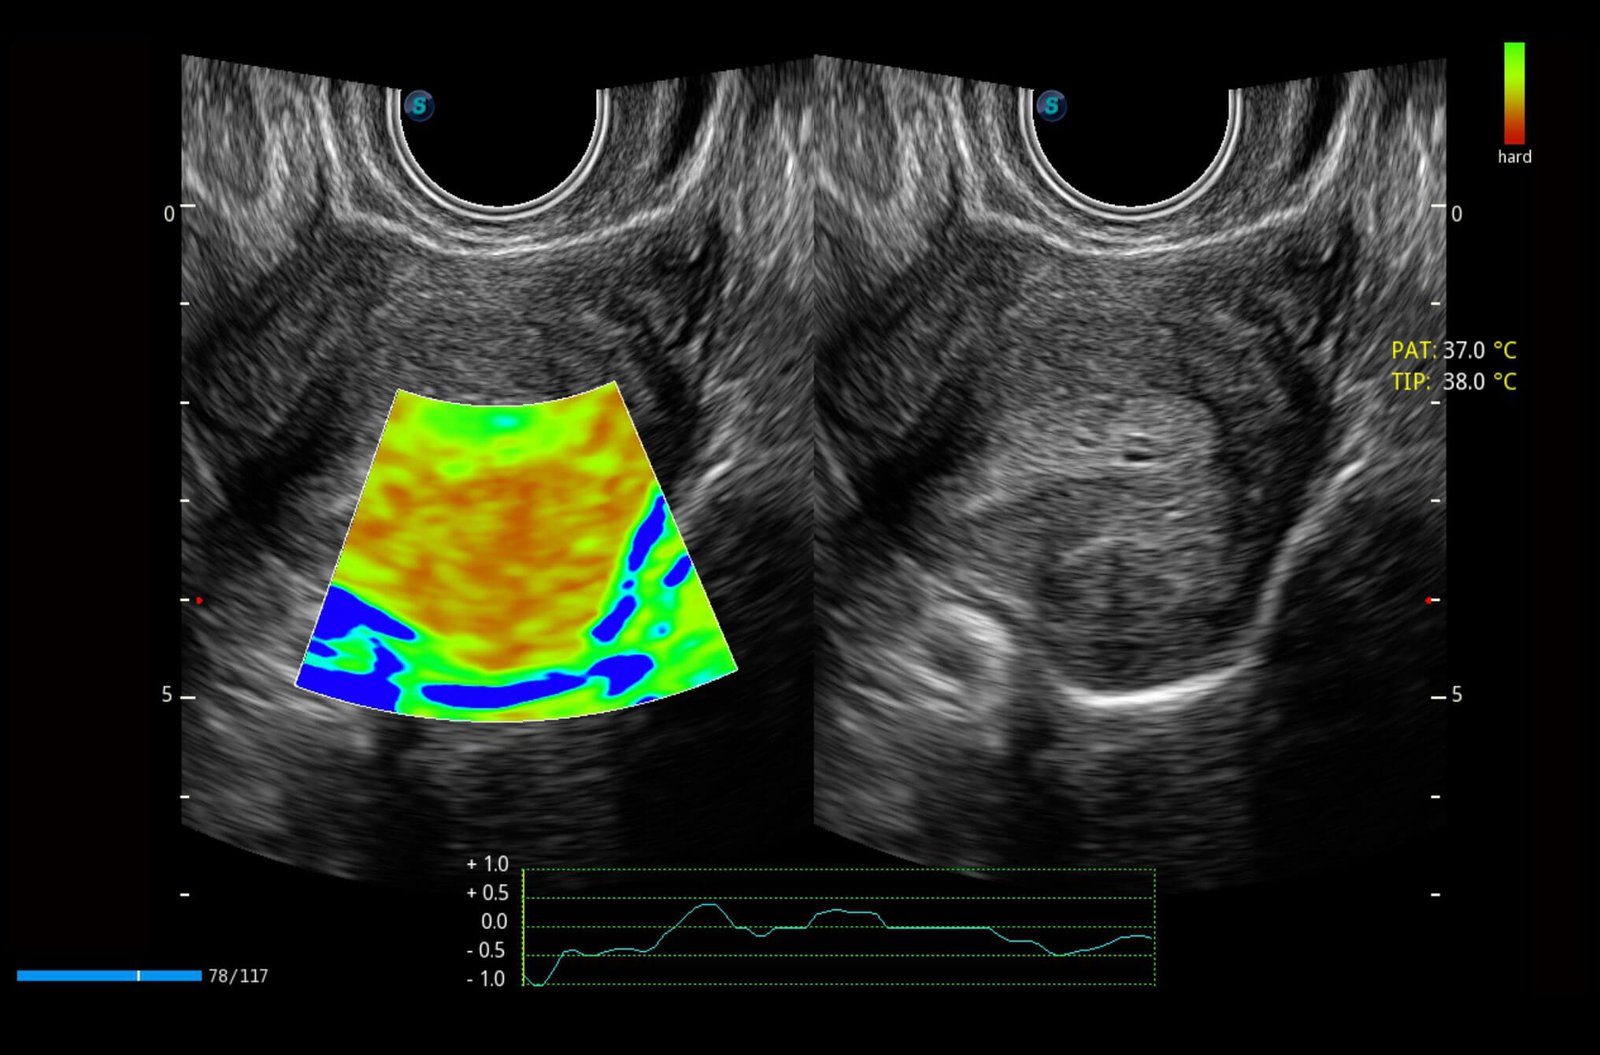

Single Crystal Convex C1-6

Perfect uniformity of crystal alignment generates pure imaging with better penetration and higher S/N ratio, especially for difficult patients mainly in abdominal and OB applications.